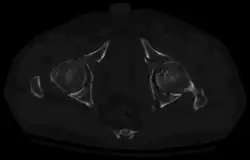

High anterior column fracture 3 D CT scan picture -

High anterior column fracture after fixation with screws and plates